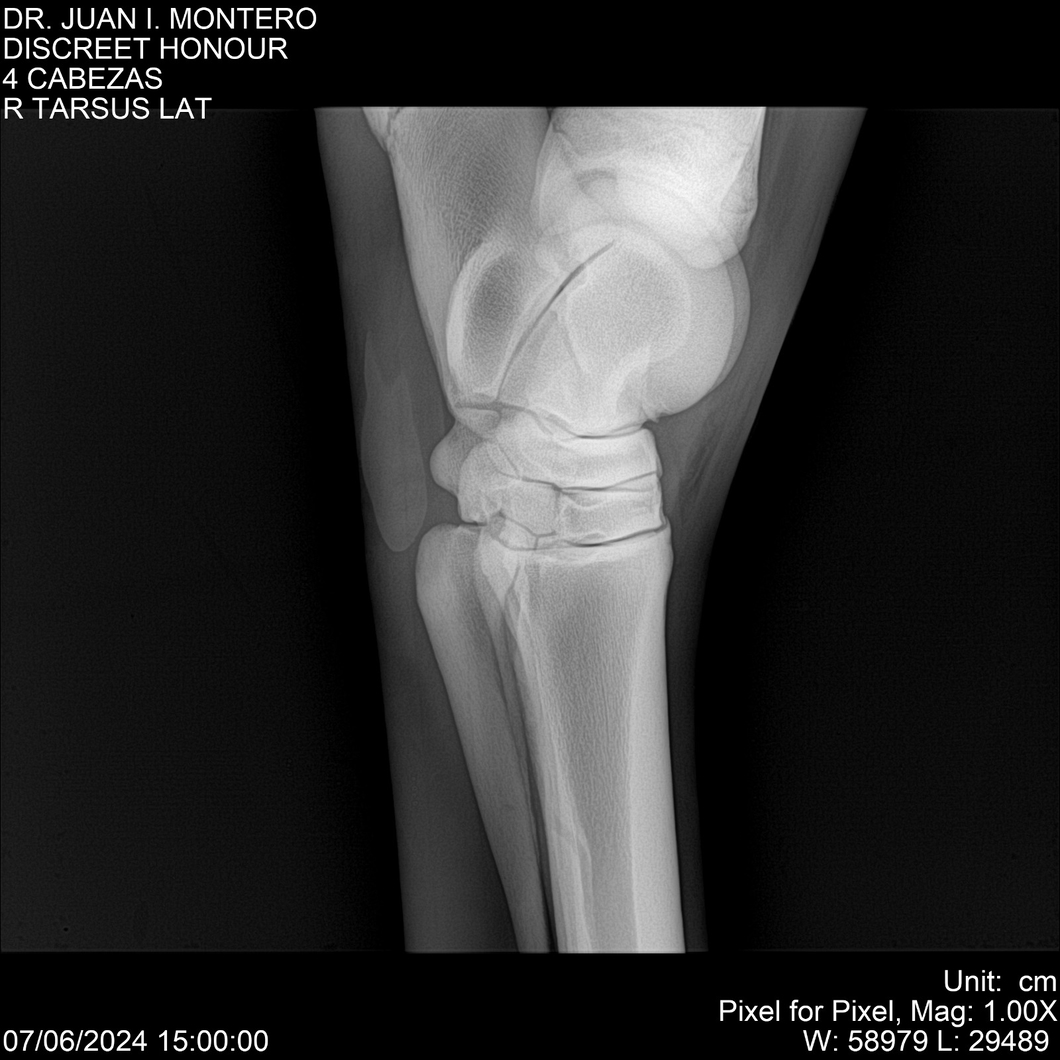

LOTE 6, DISCREET HONOUR 🔥 🔥 🔥 Lote Anterior Volver al remate Lote Siguiente Ficha Contacto Montevideo - Ficha del Lote Identificador: #281093 Categoría: Yeguarizos Montevideo - 82 Visualizaciones ClicData Contacto Empresa: Abelenda N. R., Walter Hugo Nombre*: Teléfono* : E-mail* : Mensaje Enviar Registrese gratis Este contenido Exclusivo está disponible sólo para usuarios registrados Ingresar